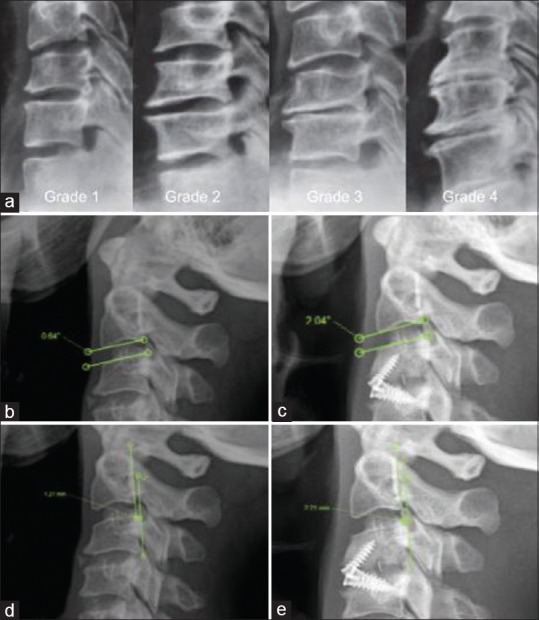

Subjects and methods: We analyzed 63 patients with ACDF with a minimum of 2 years of follow-up. In the imaging evaluation, sagittal balance parameters were included, as well as radiographic parameters that target the development of ASDeg. In addition, discrimination was made between arthrodesis techniques.

Results: Patients with postoperative imbalance presented with radiographic ASDeg at a rate of 26% (n = 5) versus 22% (n = 9) in patients with postoperative balance, this difference was not significant (P = 0.7). In those who underwent surgery with plate, we found that 23% (n = 4) developed ASDeg versus 22% (n = 1) of patients with anterior cervical arthrodesis with cage-plate and 27% (n = 10) of patients who underwent interbody device surgery, with this difference being nonsignificant (P = 0.7).